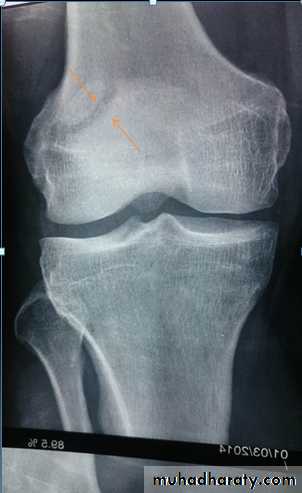

X-ray:

One or both condyles may fracture with varying degrees of comminution.

C-T:

scan in complex fractures.